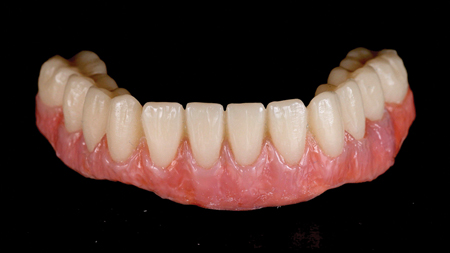

An Alternative Prosthetic Design for Lower Full-Arch Implant Restorations

Frontal view of finished prosthesis.

Replacing a full set of teeth with dental implants, especially in the mandible, has been well researched and is often a life-changing treatment for many patients. This treatment involves the extraction of failing teeth, immediate implant placement, immediate loading of the implants with a fixed provisional prosthesis, followed by the fabrication of a definitive prosthesis … Read more